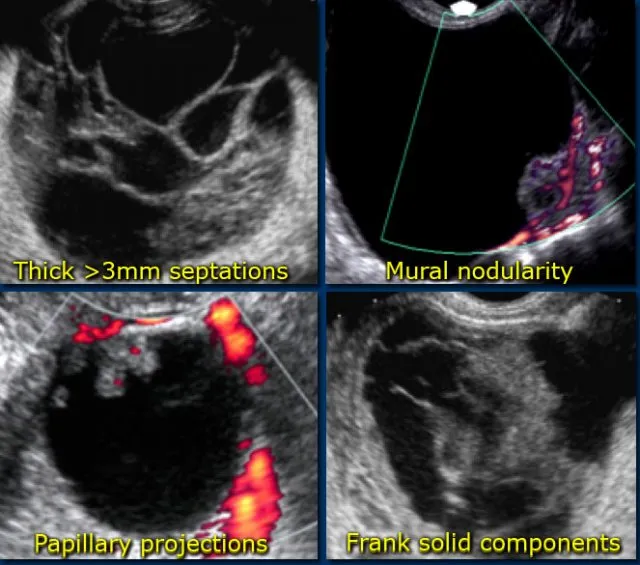

- Malignancy Red Flags (US):

- Solid irregular components, thick septa (>3 mm), papillary projections (≥4).

- Ascites, ↑vascularity (low RI <0.4).